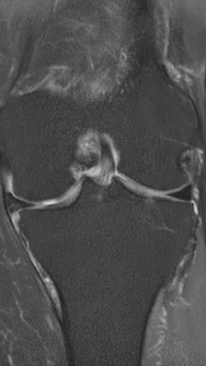

Асептический некроз коленного сустава

4 процедуры ФДТ, 9 процедур MBST, 15 процедур ИПМТ

Параметры изменяются в зависимости от процедуры

Дата публикации: 22.08.2025 14:27:03

3 процедуры ФДТ, 9 процедур MBST, 15 процедур ИПМТ

Дата публикации: 22.08.2025 14:26:54